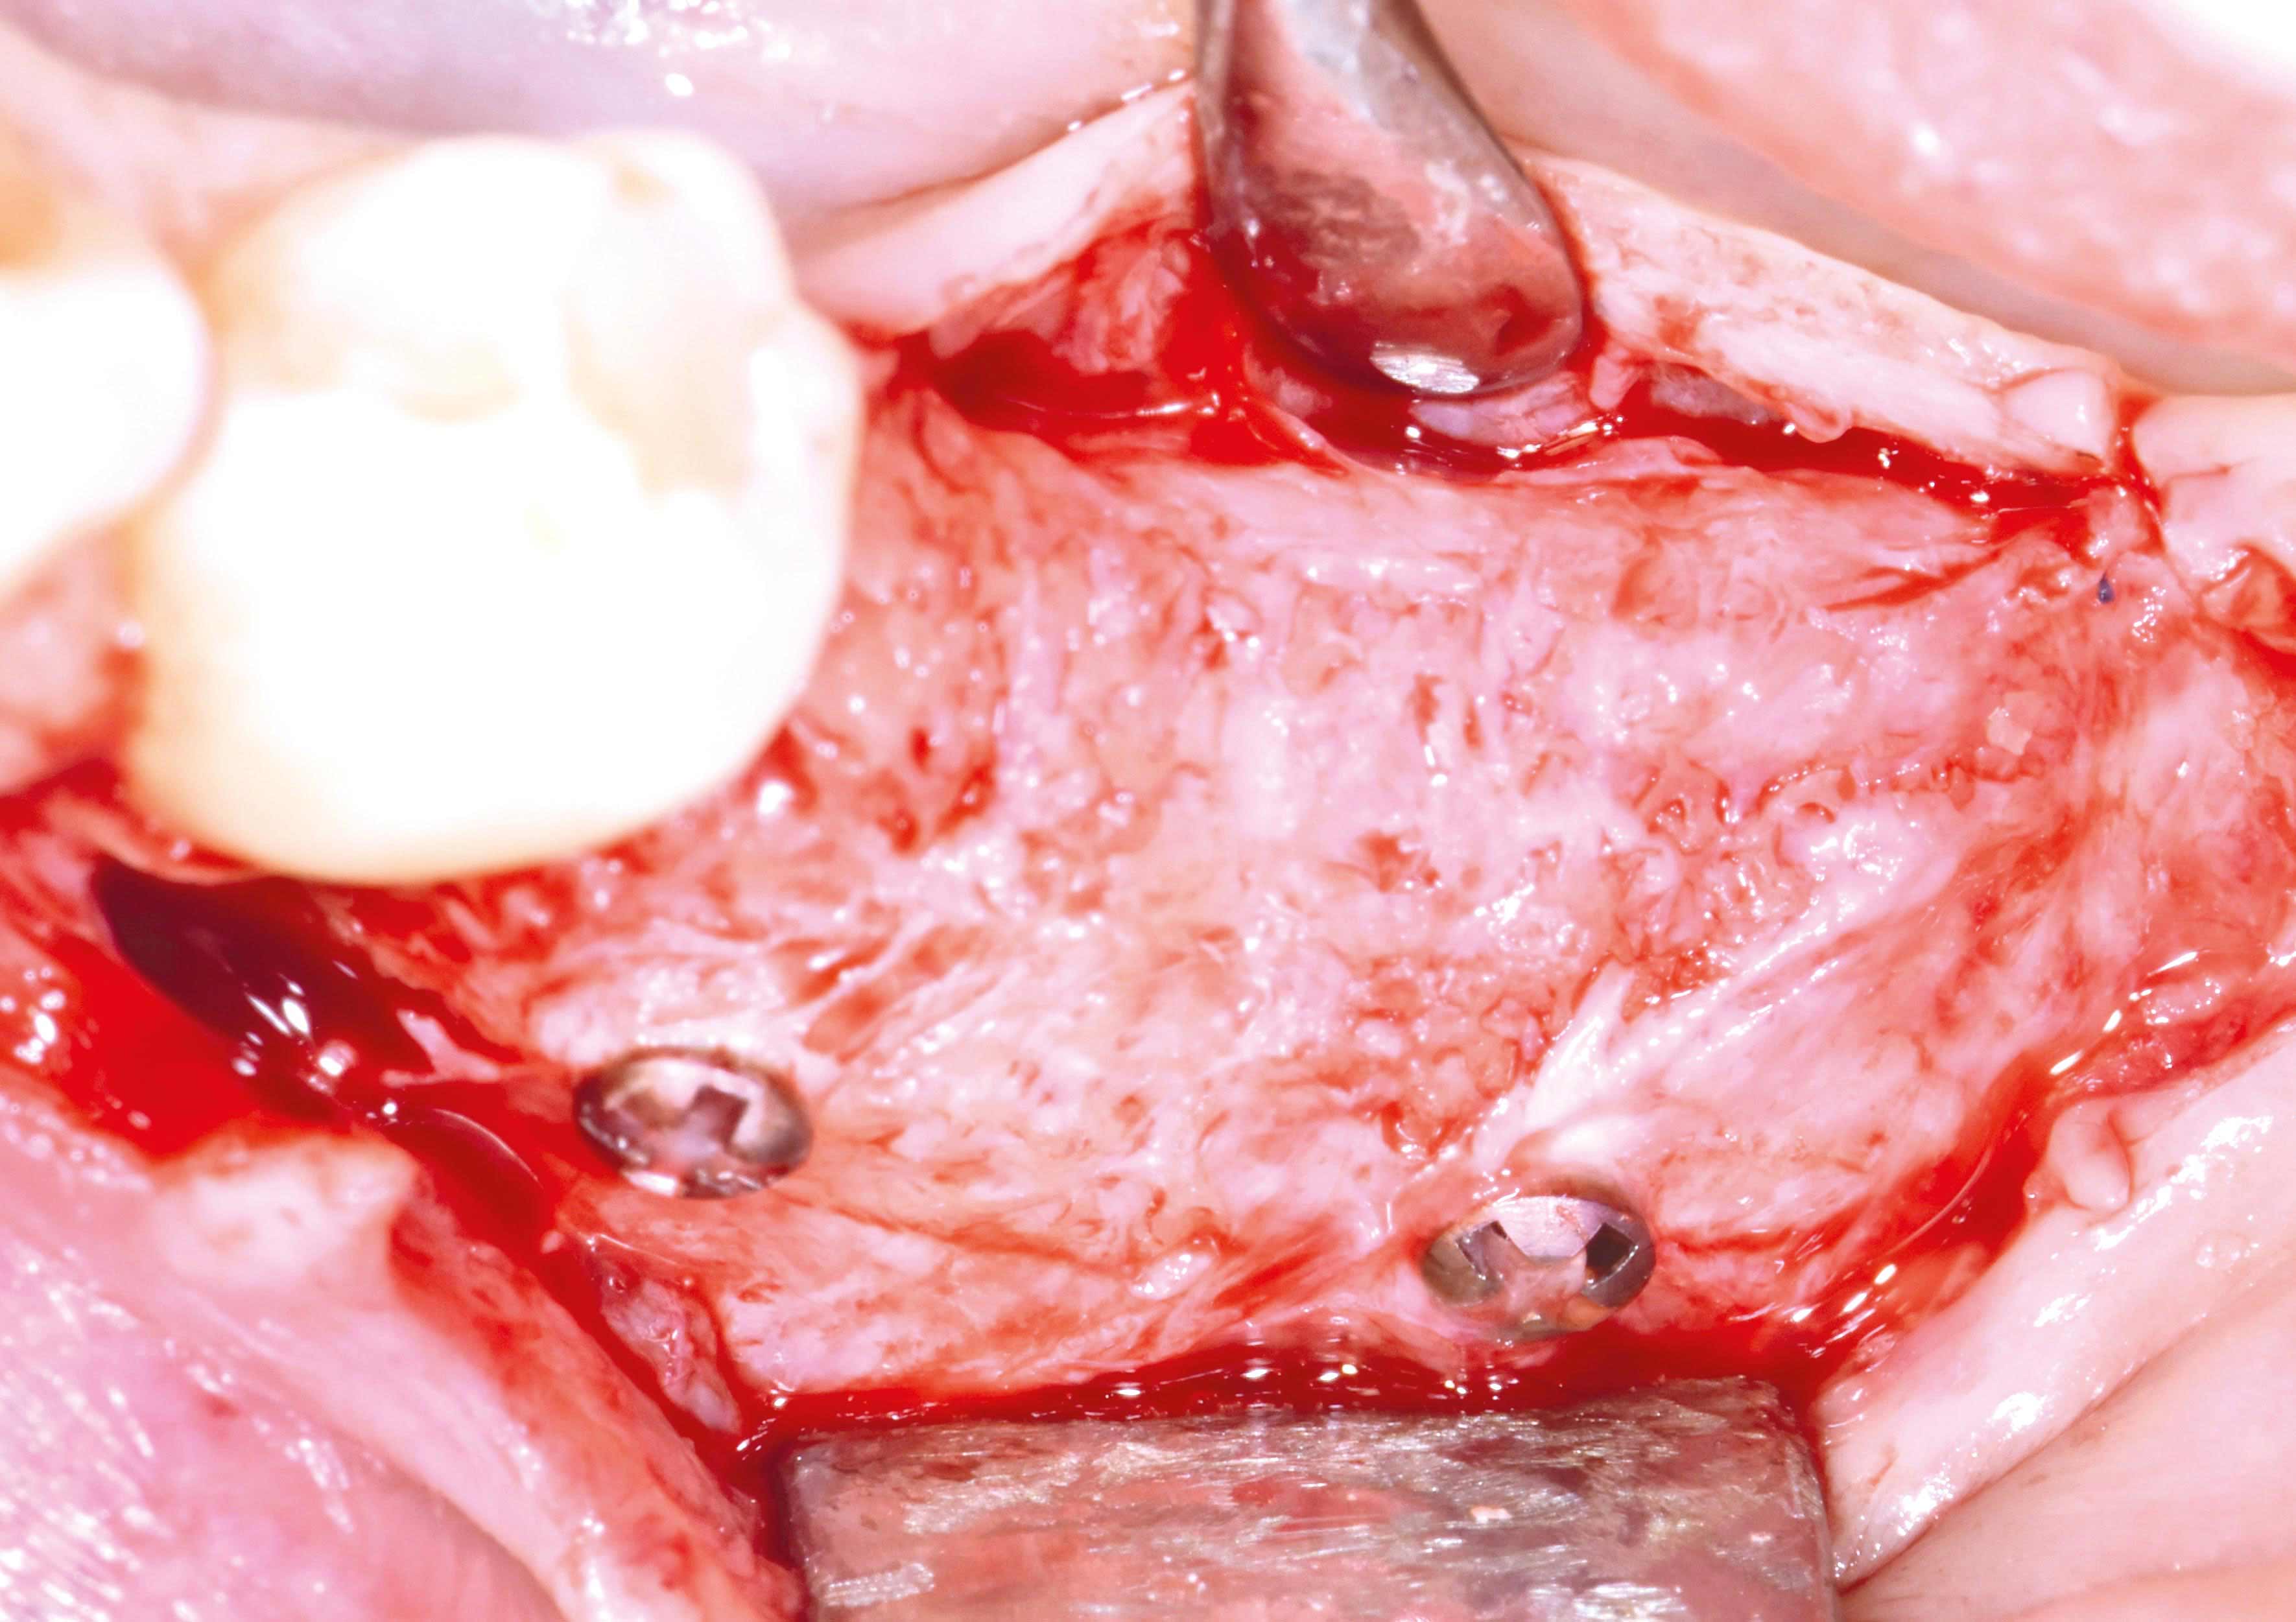

Three implants placed in a narrow posterior mandible